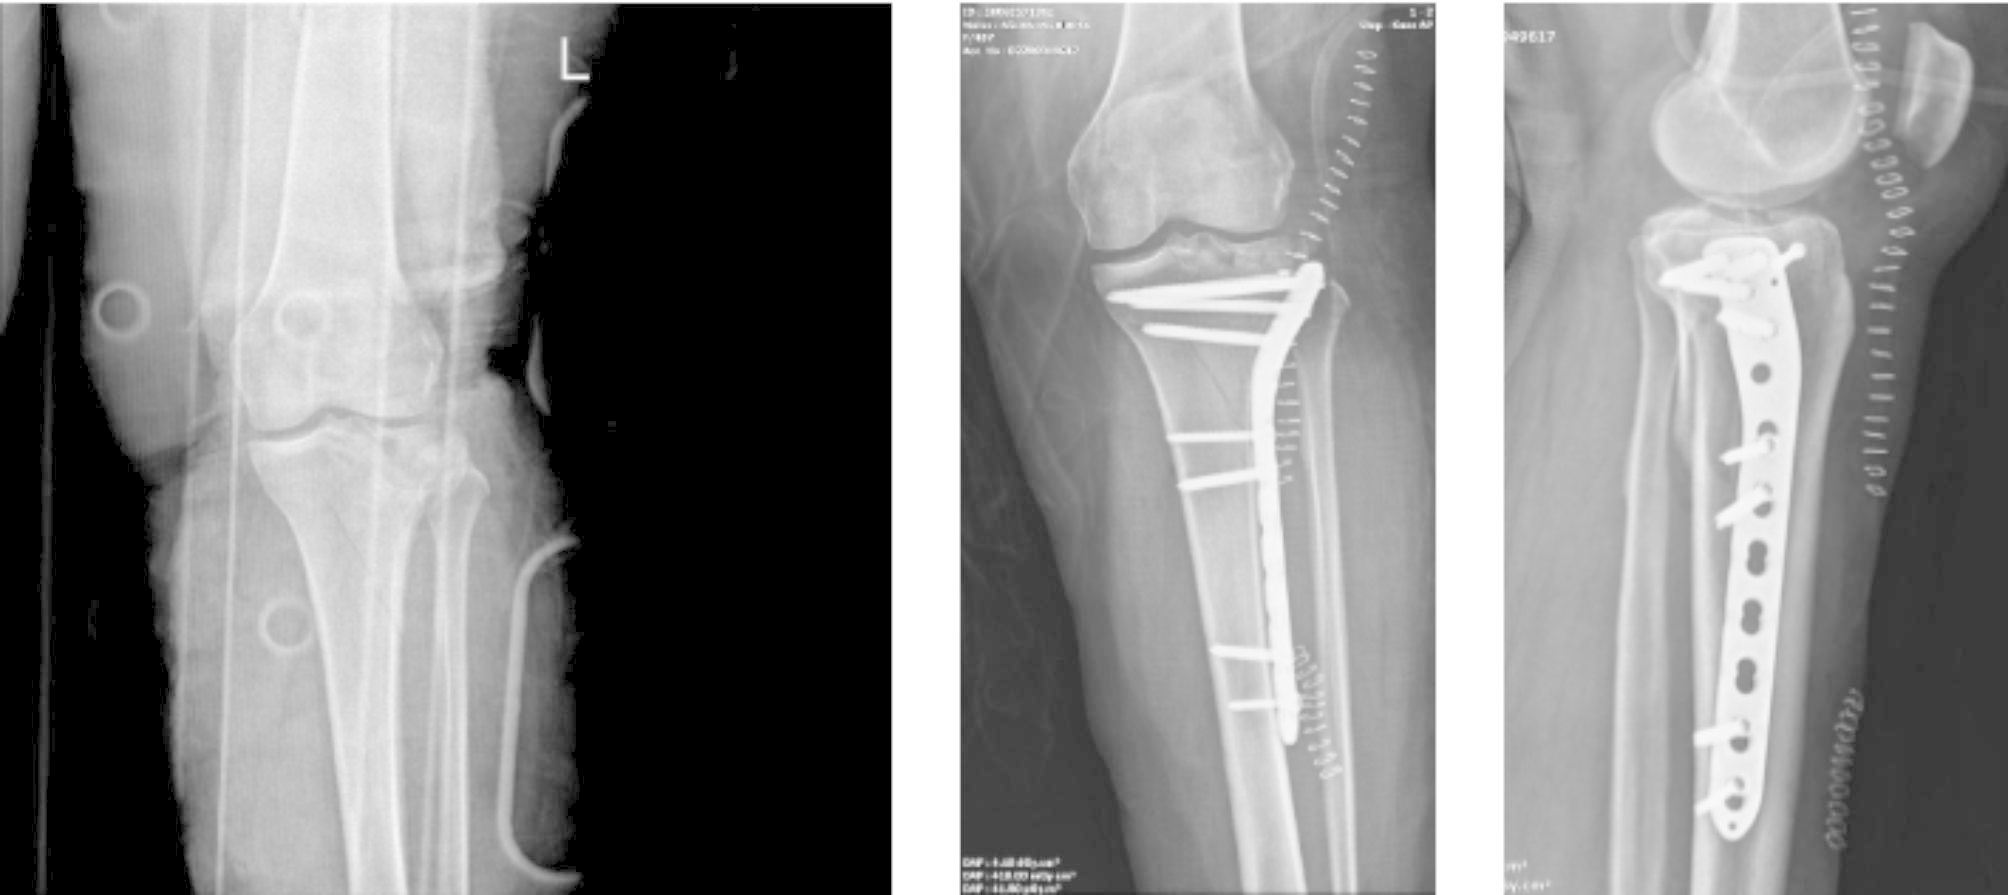

To the best of our knowledge, this study is the first to have evaluated orthopedics-related injuries after e-scooter accidents in Turkey. In particular, people’s avoidance of public transport during the COVID-19 pandemic, the transition to a shared e-scooter system in many big cities, and cheap and easy use have made the use of e-scooters widespread among the public. However, the number of accidents has increased rapidly. As seen in this study, various traumas that affect human life, including death, may occur after using e scooters. From the study results, it was observed that 32 (61.5%) patients were operated on due to fractures and dislocations after the accident (Figs. 2 and 3). In a study by Cruz et al., surgery was performed on 30.1% of the patients and it was shown that the use of e-scooters caused high-energy injuries such as femoral neck fractures, open lower and upper extremity fractures, and fracture-dislocations [10]. In another study, major musculoskeletal injuries were observed at the rate of 36% after e-scooter accidents [11]. Mayhew et al. reported that orthopedic injuries after e-scooter accidents were the most common pathology at the rate of 20.6% [1]. Similar to the current study, previous studies have shown that the most common fractures after an e-scooter accident are upper extremity fractures [8, 10, 12].

Fig. 3

A 45-year-old male patient with tibial plateau fracture after falling from e-sccoter. (A) Preoperative antero-posterior radiography, (B) Postoperative antero-posterior radiography, (C) Postoperative lateral radiography